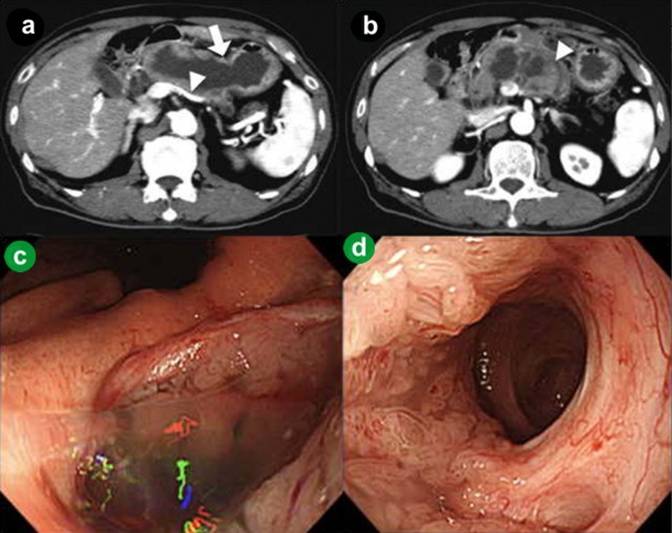

A 75-year-old man was admitted to the hospital because of acute onset of severe epigastric pain and body weight loss. On physical examination, palpable mass and tenderness of upper abdomen was noted. Laboratory studies revealed elevated C-reactive protein (7.0 mg/dL; reference range: 0-0.5 mg/dL), CEA (39.7 ng/mL; reference range: 0-5 ng/mL), CA 19-9 (62.3 U/mL; reference range: 0-37 U/mL) and HbA1c (13.2%; reference range: 3.4-5.8%). Results of complete blood count, plasma levels of electrolytes, tests of coagulation, amylase, lipase, kidney and liver function were within normal limits. Computed tomography (CT) and magnetic resonance imaging (MRI) of the abdomen showed a markedly dilated main pancreatic duct (45 mm), a papillary tumor (20 mm in diameter) protruding into the main pancreatic duct of the distal pancreas and splenic vein obstruction (Figure 1abc). On duodenoscopy with a lateral viewing of endoscope, mucus was discharged from the enlarged papilla of Vater (Figure 2a). Peroral pancreatoscopy was performed, revealing the papillary tumor on the main pancreatic duct (Figure 2b). Pathological examination of biopsy specimens of the tumor showed papillary mucinous adenoma (Figure 2c).

Figure1. a. Computed tomography (CT) showed a markedly dilated main pancreatic duct (45 mm, arrow) and splenic vein obstruction (arrowhead). b. CT showed a papillary tumor (20 mm in diameter) protruding into the main pancreatic duct of the distal pancreas (arrowhead). c. Magnetic resonance cholangiopancreatography (MRCP) showed a markedly dilated main pancreatic duct. |

One year later, CT revealed increased size of the papillary tumor, the main pancreatic duct penetrating to the stomach and reperfusion of the splenic vein (Figure 3ab). On gastroduodenoscopy, mucus was discharged from the gastropancreatic fistula on the lesser curvature of the middle gastric body (Figure 3c). Suction of the mucus enabled us to pass an endoscope into the dilated main pancreatic duct through the fistula and directly examine the lumen of the main pancreatic duct and the papillary tumor adjacent to the fistula (Figure 3d). This unique examination allowed us to see the whole lumen of the dilated main pancreatic duct, revealing that the papillary surface pattern was localized within the elevated lesion and no other lesions were found on the main pancreatic duct. Pathological examination of biopsy specimens of the tumor again showed papillary mucinous adenoma. The absence of malignant cells suggested mechanical penetration rather than invasive penetration. And it is likely that the penetration led to decreased inner pressure of the main pancreatic duct resulting in reperfusion of the splenic vein. Despite these imaging findings, he remained asymptomatic and was followed without treatment.

Figure 3. a. Computed tomography (CT) showed the main pancreatic duct penetrating to the stomach (arrow) and reperfusion of the splenic vein (arrowhead). b. CT showed increased size of the papillary tumor in the main pancreatic duct. c. Gastroduodenoscopy showed gastropancreatic fistula on the lesser curvature of the middle gastric body. Mucus was discharged from the fistula. d. Suction of the mucus enabled us to pass an endoscope into the dilated main pancreatic duct through the fistula and directly examine the lumen of the main pancreatic duct and the papillary tumor adjacent to the fistula. |